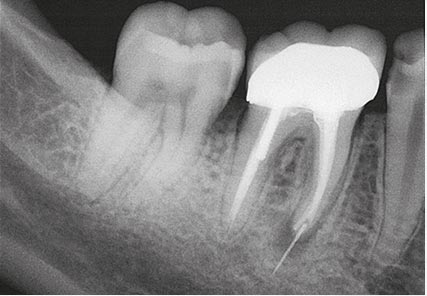

Breakage of endodontic files during treatment can result in serious complications and jeopardize the outcome of treatment. When using nickel-titanium (Ni-Ti) files, prevention of file breakage is complicated by the fact that these files rarely demonstrate visible evidence of cyclic fatigue and torsional stress and do not show wear before breakage.1 In the event that a file does break, removal can be difficult due to anatomical considerations, and the long-term prognosis of the tooth can become guarded.

An unfinished root canal will eventually cause many problems. The most common complication is that the tooth will begin to cause pain. There is also a risk that the tooth may fracture or cause a potentially dangerous swelling of the gum.

The greater the amount of uncleaned and unfilled canal space that remains after a root canal procedure, the greater failure rate. The challenge for clinicians is to decide to what point endodontic obturation should be directed in the given procedure. Cleaning, shaping and obturating less than the entire root canal space has the potential to or certainly could leave uncleaned and unfilled space, especially if the root is obturated to levels determined by arbitrary anatomic averages and not the true apical foramen.

Root canal overfills occur when a dentist is obturating (filling) a root canal. If the gutta percha(canal filling material) extrudes out the end of the root it is called an overfill. Sometimes, the gutta percha may have slipped through because it was not of sufficient diameter to bind at the apex. If a guttapercha that is too small is used, it can slip thru the tiny apical foramen (a hole at the tip of the root) and the resulting over fill may or may not form good seal . If the gutta percha does not adequately obturate (seal) the apex, then bacteria can repopulate any left over space. This bacterial colonization is most likely the actual cause of most endodontic failures associated with overfills.